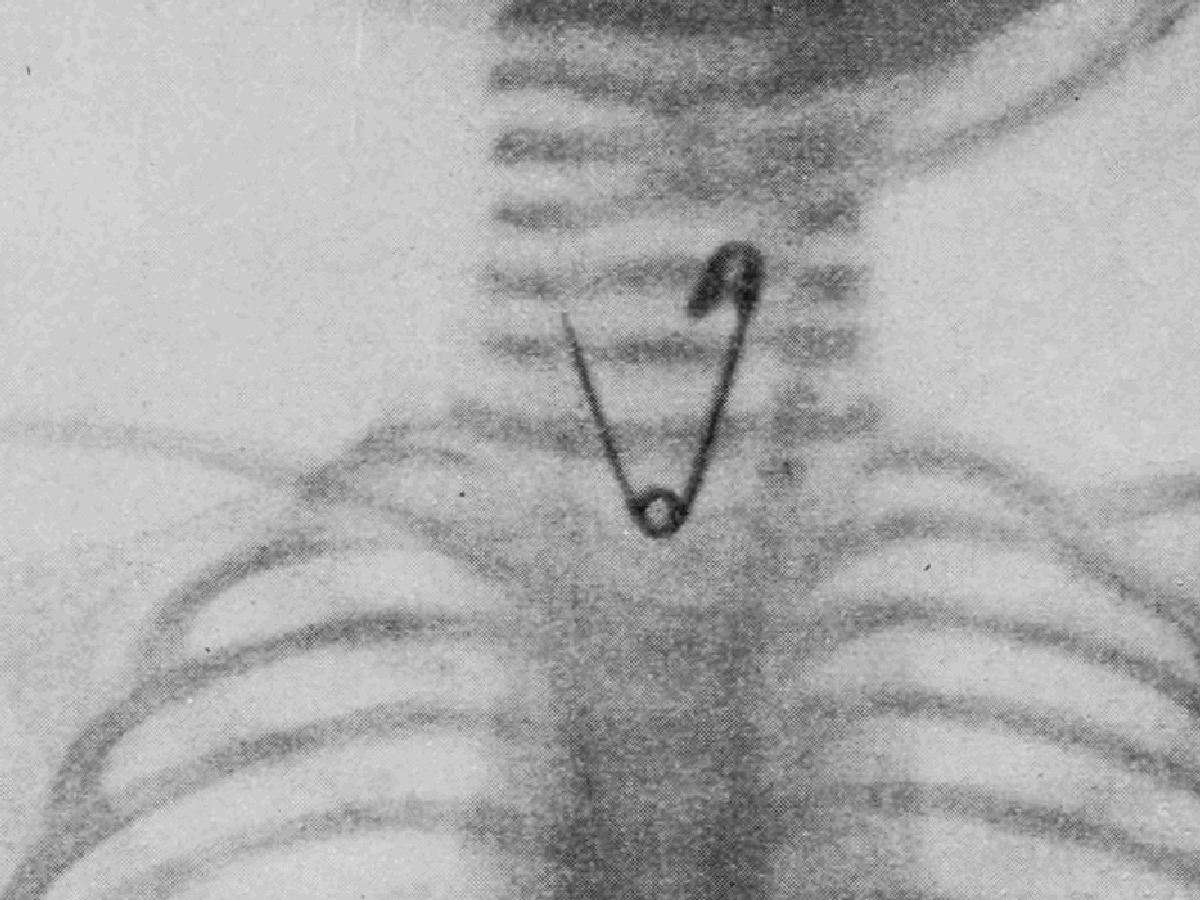

Radiografia feita do primeiro paciente, antes do procedimento cirúrgico. Após nossa análise, dois marcadores, em forma de 0 e 1, foram fixados sobre a pele da criança. O marcador Fonte: acervo pessoal.